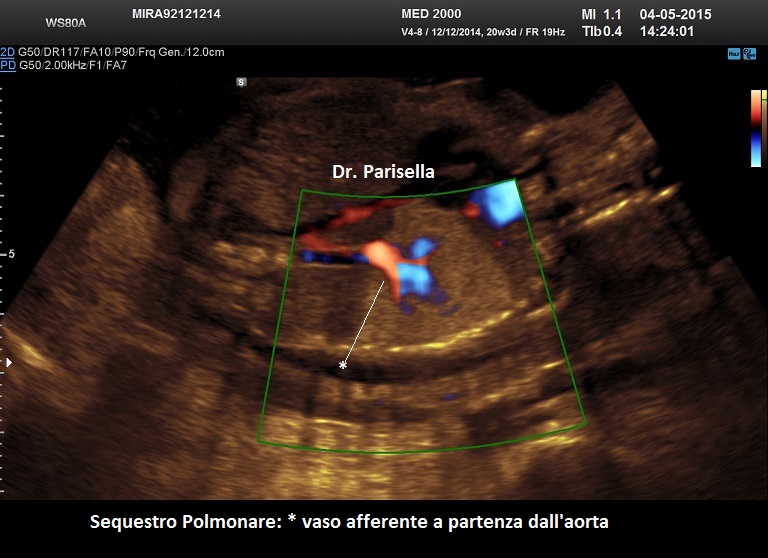

La diagnosi differenziale deve essere posta con il Sequestro polmonare:  in questo caso è dirimente il riscontro di un vaso afferente originato dall'aorta nel sequestro polmonare a differenza della MACP in cui la massa è irrorata da diramazioni dell'arteria polmonare.

• extra-lobare: è una forma più rara ed è quella classicamente diagnosticata in epoca prenatale; nel 90% dei casi è sopra-diaframmatica, nel 10% è sotto-diaframmatica. Caratteristicamente presenta un vaso afferente a partenza dall'aorta toracica o addominale.

Si presenta come una lesione iperecogena localizzata più frequentemente al lobo inferiore del polmone sinistro, più raramente in sede sottodiaframmatica. Al Color-Doppler si evidenzia il vaso afferente a partenza dall'aorta toracica o addominale.

La diagnosi differenziale deve essere posta con la MACP: in questo caso è dirimente il riscontro di un vaso afferente originato dall'aorta nel sequestro polmonare a differenza della MACP in cui la massa è irrorata da diramazioni dell'arteria polmonare.